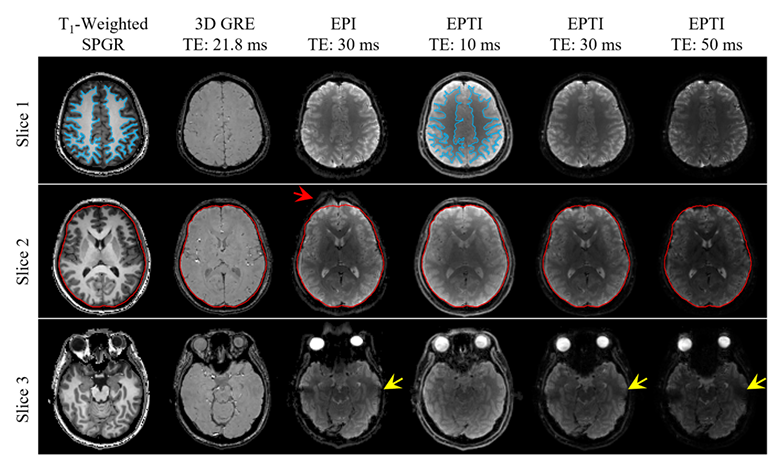

1. Rapid quantitative susceptibility mapping using single-shot echo planar time-resolved imaging.png

Bai H, Dai K, Li Z, Solomon E, Wei H, Xu Z, Chen H, Zhang Z

Physics in Medicine and Biology, 2025